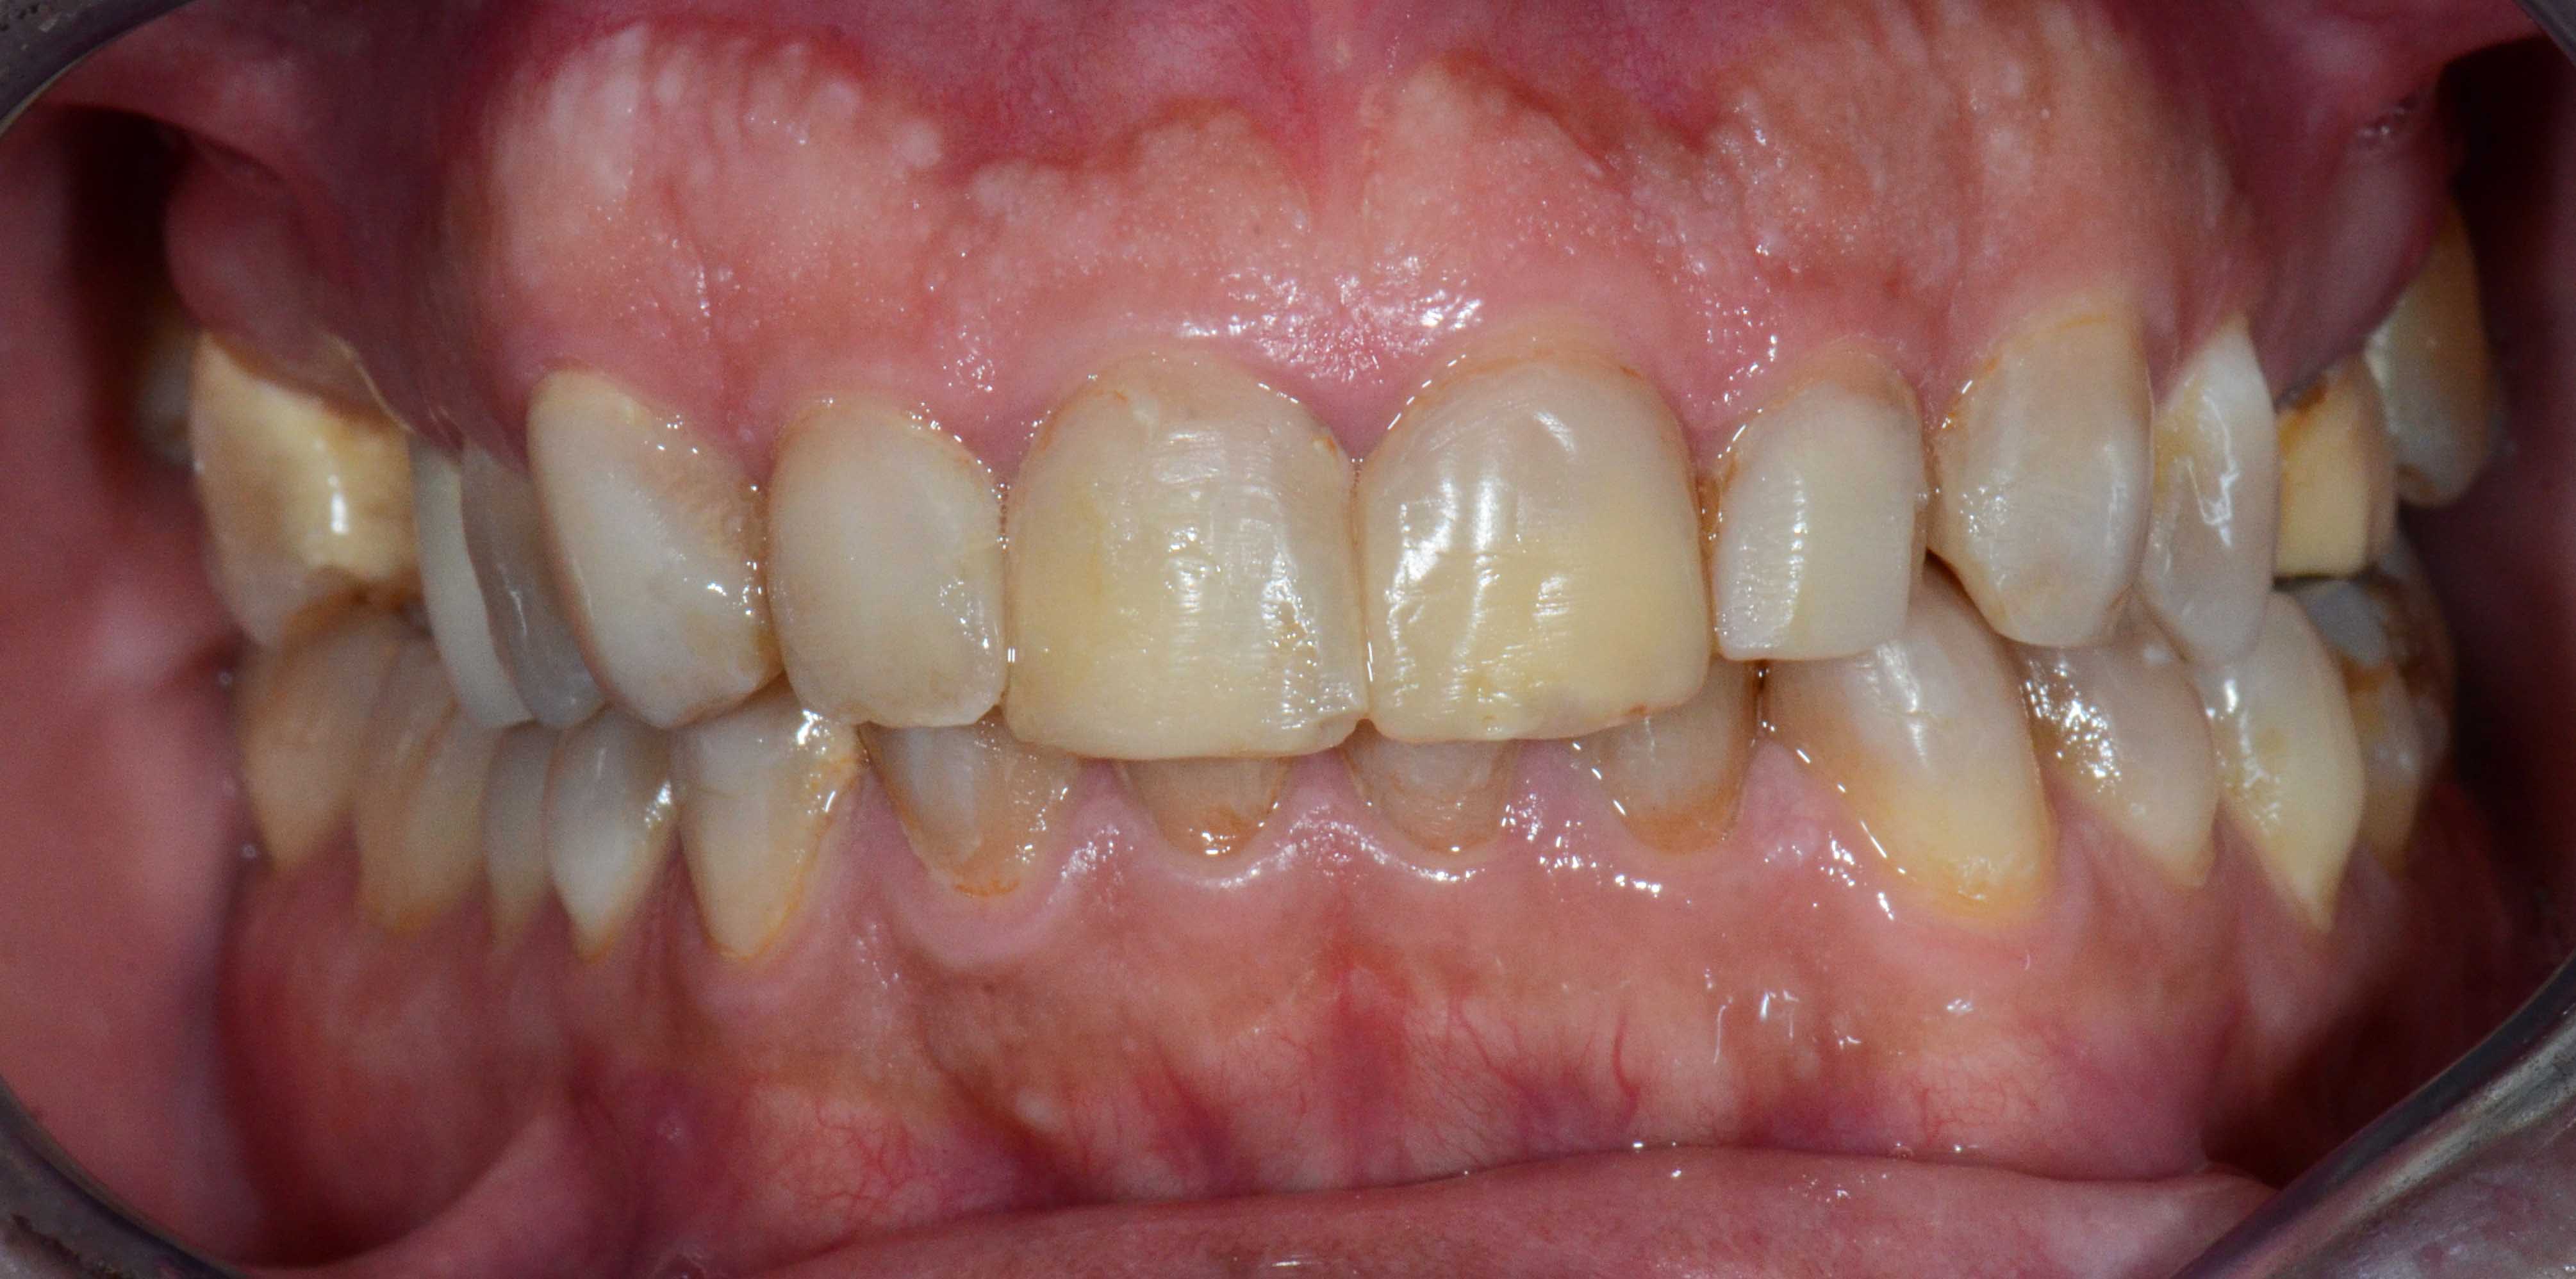

Paciente com limitações funcionais e estéticas graves

Reabilitação Complexa - Tratamento

Mantiveram-se os dentes naturais remanescentes que tinham bom prognóstico e com Aparelho Ortodôntico fixo foram corrigidas as suas posições.

Posteriormente foi feita cirurgia para colocação de alguns Implantes.

Finalizou-se com colocação de Coroas Cerâmicas.